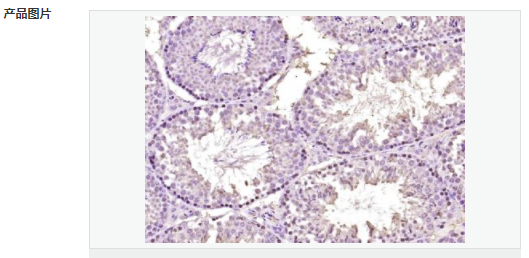

交叉反應:Human,Mouse(predicted:Rat,Dog,Pig,Cow,Rabbit) 推薦應用:IHC-P,IHC-F,ICC,IF,ELISA

產品應用ELISA=1:5000-10000 IHC-P=1:100-500 IHC-F=1:100-500 ICC=1:100-500 IF=1:100-500 (石蠟切片需做抗原修復)

免 疫 原KLH conjugated synthetic peptide derived from human SOX7:42-100/388

Widely expressed in adult and fetal tissues. Present both in mesenchymal and epithelial cells in some adult tissues, including colon. Tends to be down-regulated in prostate adenocarcinomas and colorectal tumors due to promoter hypermethylation.